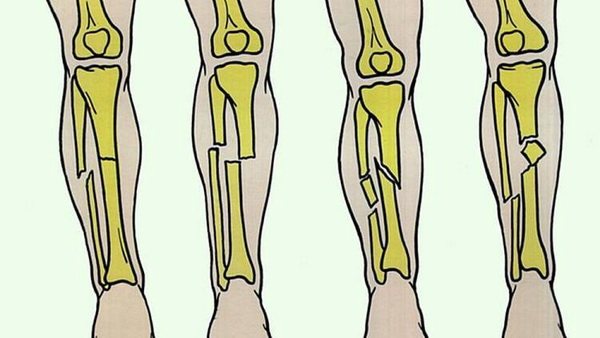

Повреждения могут иметь открытый, когда есть рана с отломками в дне или закрытый характер (без повреждения кожных покровов), а также быть со смещением или без него. Также переломы могут быть без отломков или многооскольчатыми. Повреждение может быть по типу трещины или неполными, а также на весь диаметр кости. Выделяют переломы костей голени:

Переломы костей Г. бывают открытые и закрытые. Выделяют переломы мыщелков большеберцовой кости, диафизов и лодыжек, а также головки малоберцовой кости. Переломы верхнего и нижнего концов костей Г. относятся к внутри- и околосуставным (см. Голеностопный сустав, Коленный сустав). Переломы костей Г. в верхней, средней и нижней трети диафиза могут быть косыми или спиралевидными (рис. 2). Повреждаются большеберцовая кость либо обе кости Г. в результате как бы скручивания Г. при фиксированной стопе, падения на ноги и т.п. Реже отмечаются поперечные или оскольчатые переломы костей голени (удар, сдавление, сгибание).

Рис. 2. Варианты переломов диафизов костей голени: а — перелом без смещения отломков большеберцовой кости; б — перелом со смещением отломков большеберцовой кости; в — косой перелом; г — оскольчатый перелом.